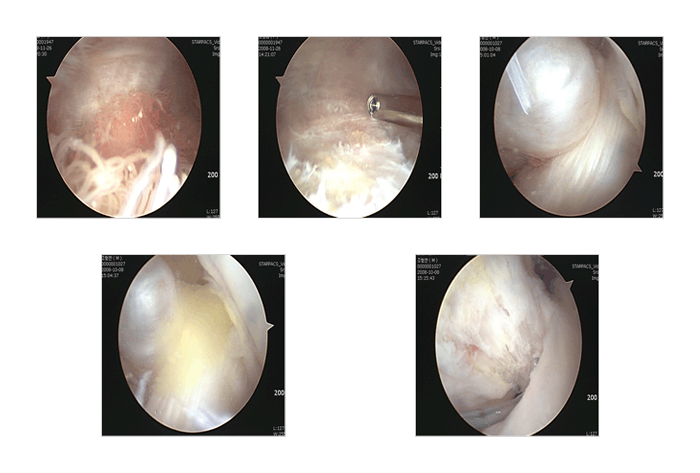

퇴행성 관절염

관절염은 계속 진행하는 질환이기 때문에 관절염 자체를 관절경 수술을 통해 완치시키기는 어렵습니다. 하지만 심한 연골판 파열을 동반한 경우나 떨어져 나간 연골 파편이 유리체가 되어 관절 내에 있을 때, 심한 염증 반응으로 물이 계속 찰 때는 관절경 수술을 통해 증상을 호전 시켜 볼 수 있으며 경증의 관절염시는 연골재생치료도 시도 해 볼 수 있습니다. 관절경 치료는 급속도로 악화되는 것을 지연시키고 증상을 호전 시키는 정도에 목적을 두어야 하고 심한 관절염은 관절경 수술보다는 인공 관절 치환술을 권유 합니다 .

활액막염

활액막염은 그 자체가 일차적인 병명 이라기보다는 다른 원인에 의해 이차적으로 발생하는 병명으로 이해하는 것이 좋습니다. 여러 가지 원인 중 류마티스 관절염이 그 하나인데 관절경을 통해 활액막 절제를 하면 붓거나 물이 차는 증상이 개선됩니다 . 하지만 류마티스 관절염도 난치성 질환으로 재발의 가능성이 높으므로 적절한 약물치료와 병행되어야 효과가 오래 지속될 것으로 생각됩니다. 화농성 관절염도 관절경을 이용한 치료 적응증 중 하나인데 약물치료로 안된다고 판단되면 비교적 응급으로 활막 절제와 세척을 하는 것이 골수염이나 다른 이차적 합병증을 막을수 있습니다. 기타 관절내 골절의 치료 , 추벽 절제, 관절내 유리체나 이물 제거 등 많은 무릎 질환이나 외상에 사용할 수 있습니다. 또한 무릎 뒤에 물혹 ( 베이커 낭종 )이 있을 시는 물혹 자체를 관절경으로 수술 할 수는 없으나 무릎 관절내에 연골판 손상등이 동반되어 있는 경우가 많으므로 이에 대한 치료가 동반되어야 합니다.

전방 및 후방십자인대 파열 - 사진